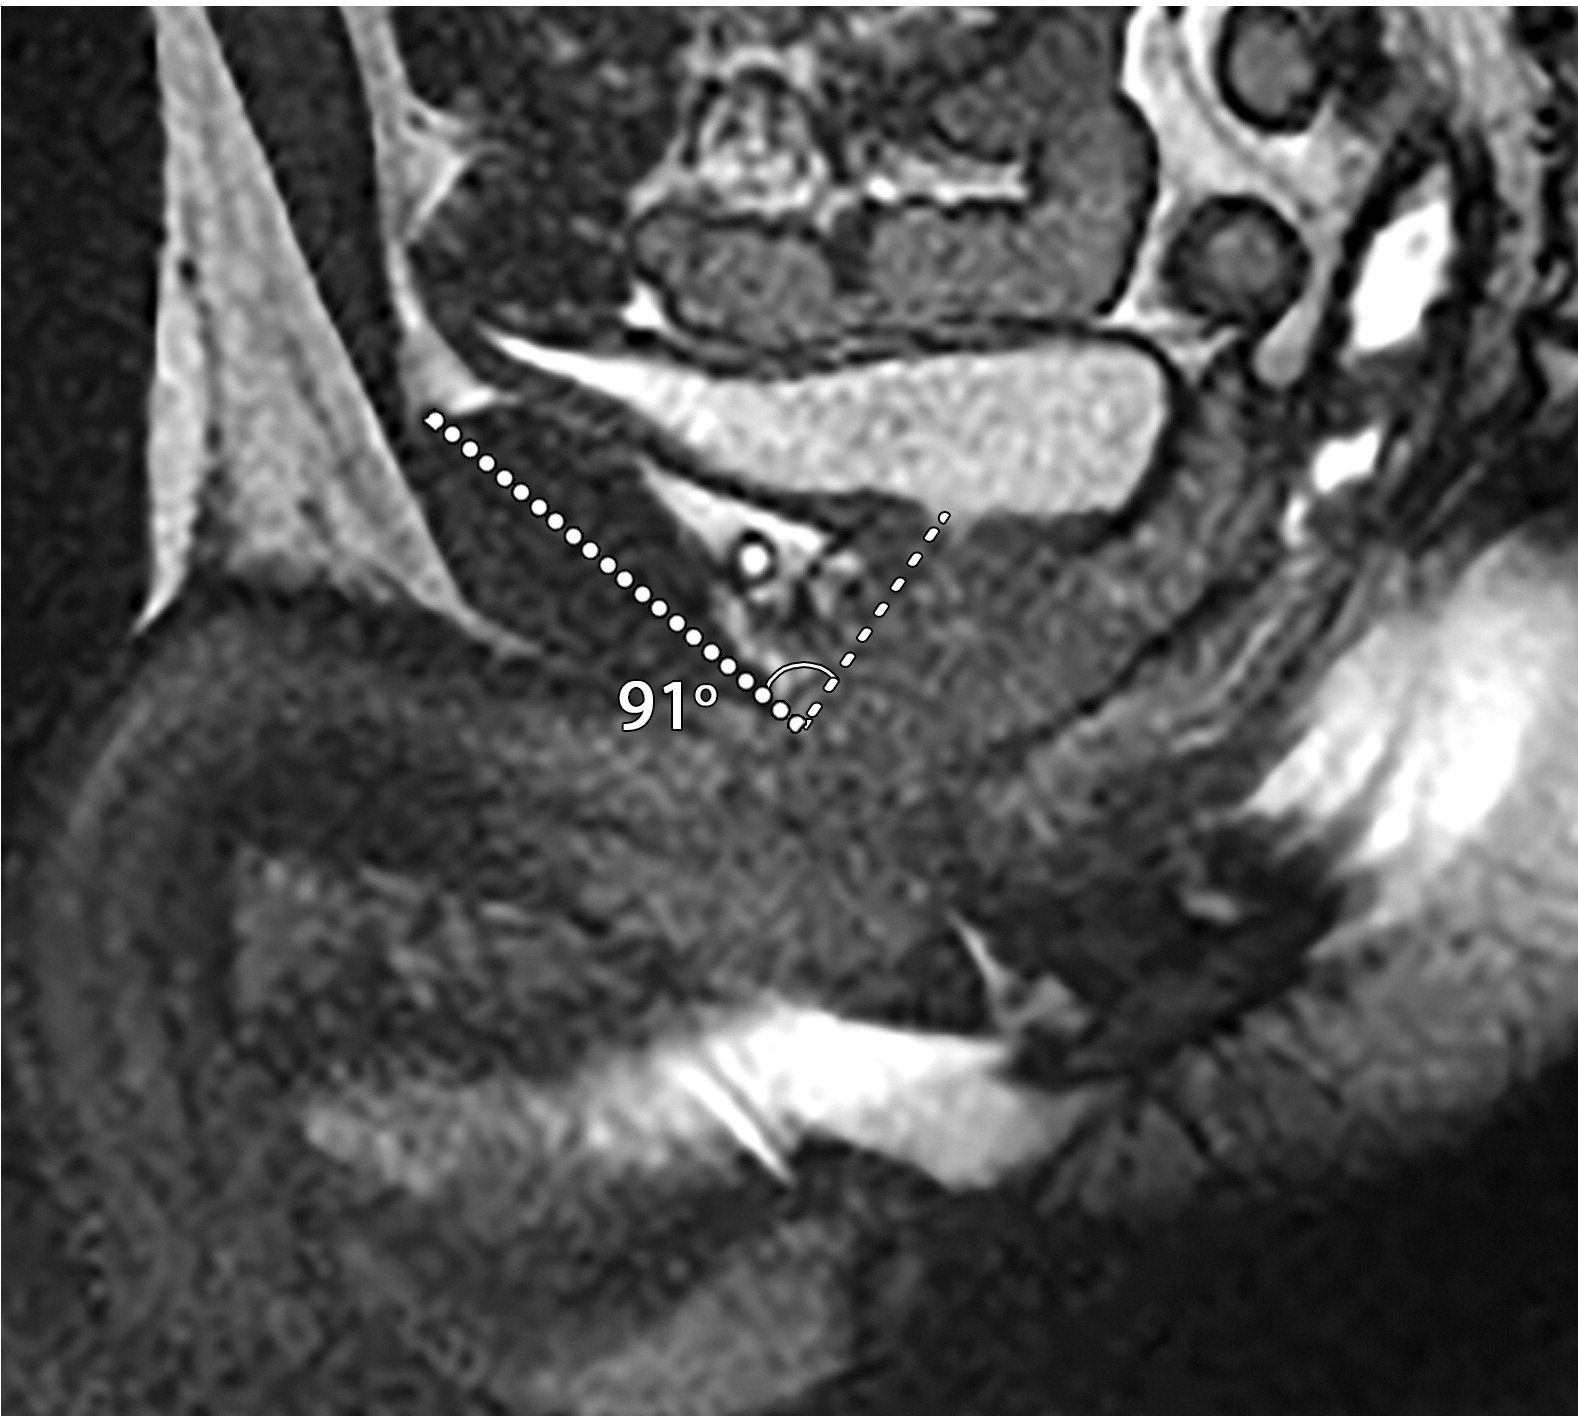

耻骨前列腺和前列腺尿道角

患者男性,39岁,良性前列腺增生,骶正中线TrueFISP MR图像显示,耻骨前列腺角从静息时的42°(a)正常增加到用力时的91°(b)。(c)67岁男性的矢状位T2加权MR图像显示前列腺-尿道角测量值为66°。